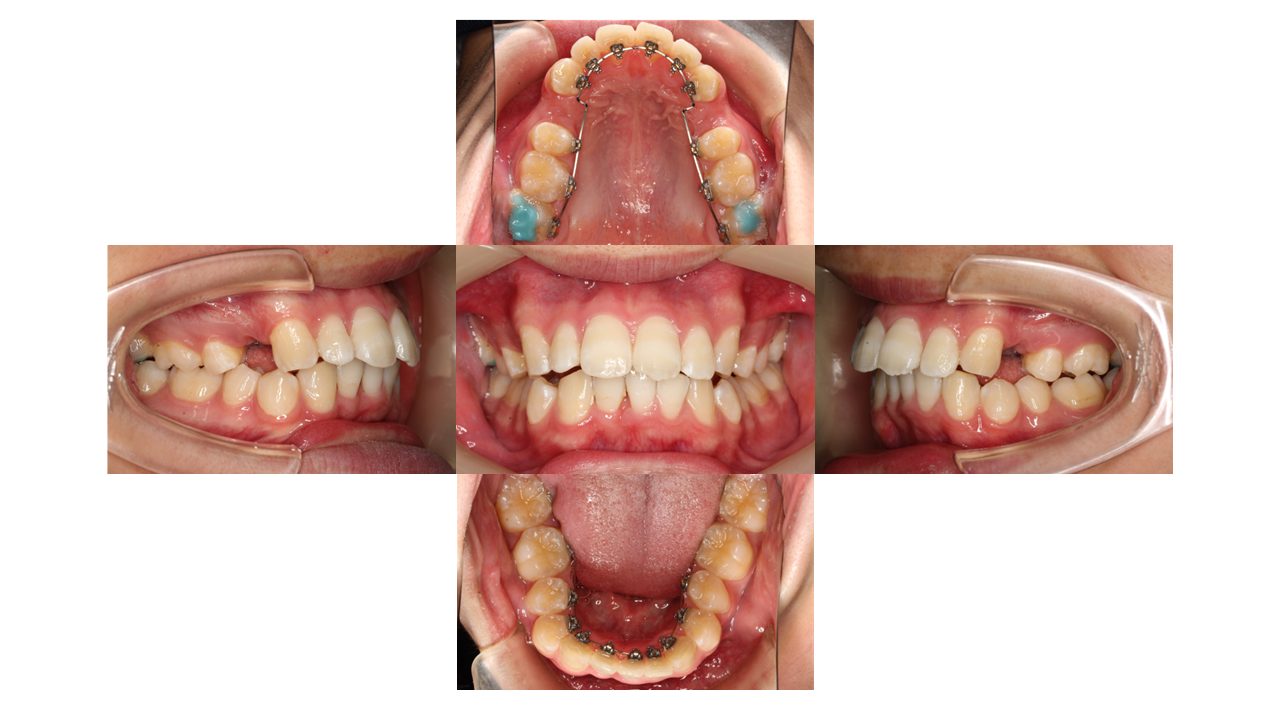

2カ月経過の口腔内の状態です。

上下前歯の凸凹が少しずつ改善してきました。